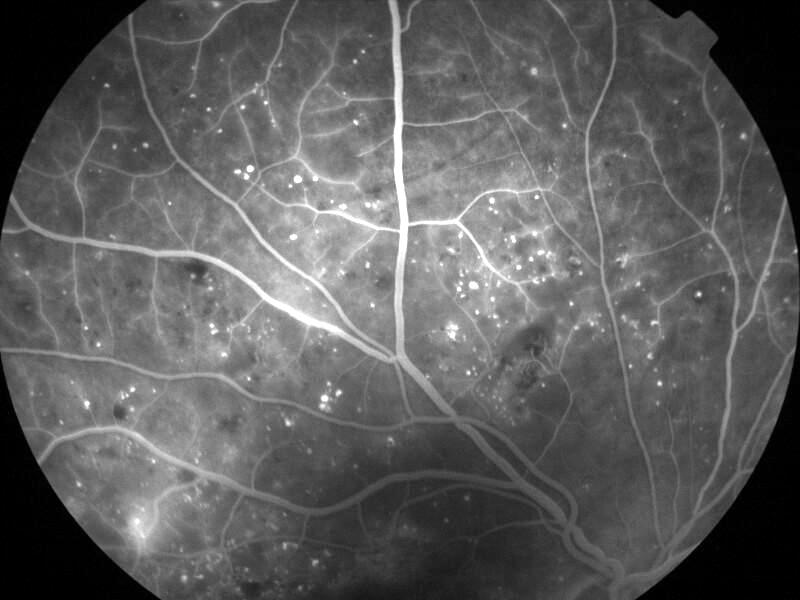

rétinopathie diabétique pré-proliférante